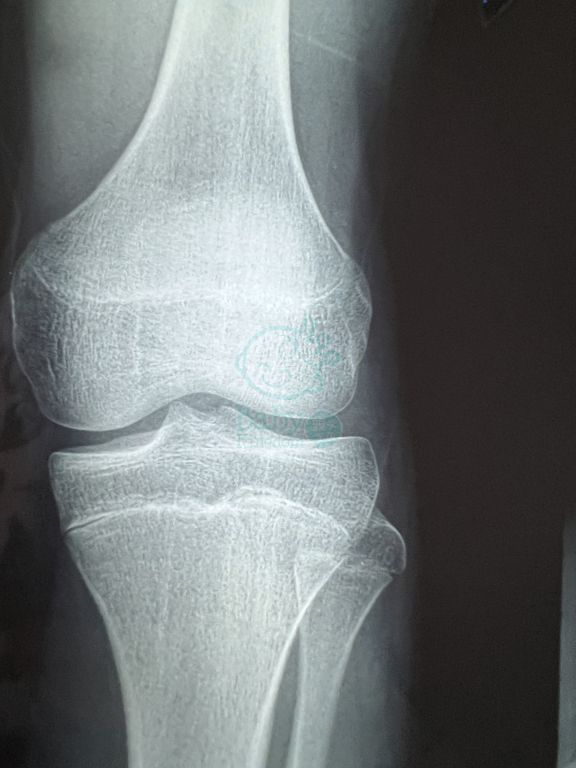

今年我個仔啱啱16歲, 但係佢對自己身高唔滿意(大約166-168), 跟住佢就瞞住我去影咗X光, 跟住我呢上個禮拜喺書櫃度搵到張X光, 我呢幾日都有上網搵關於影X光檢查仲可唔可以生高, 但係我都唔知網上嘅嘢啱唔啱, 所以想請問大家有關於呢一方面嘅嘢?